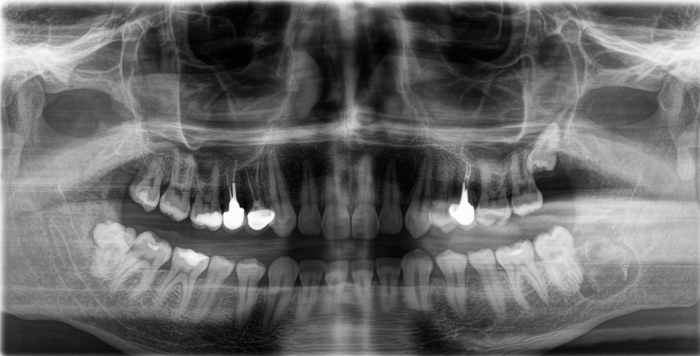

Вжух и год позади:

В целом, каких-то явных изменений нет. В подтверждение тому, что это не один и тот же снимок, вы можете обратить внимание, что на имплантате уже установлена постоянная коронка.

Добрый вечер… А что это значит?... Прекрасно видно, что фолликулярная киста начала расти и оттеснять зуб мудрости дальше в пазуху, что несколько затрудняет его удаление. Блять, подумал я, надо было сразу удалять.

Контрольный снимок после удаления: